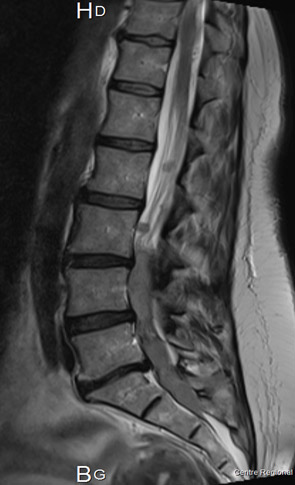

Dr Mathieu Boone CHU - Amiens

Clinique :

• Patiente de 49 ans

• Lombalgies depuis 2 ans

– Douleurs atypiques bilatérales à prédominance droite

– Topographie radiculaire L4-L5

– Recrudescence nocturne

– Restriction des loisirs mais activité professionnelle conservée

• ROT abolis et signe de Lasègue bilatéral (40°)

Pas de troubles sphinctériens ou de céphalées.

• Lésions nodulaires appendus aux racines lombaires intra-durales

• Quel diagnostic évoquer ?

• Quel bilan réaliser ?